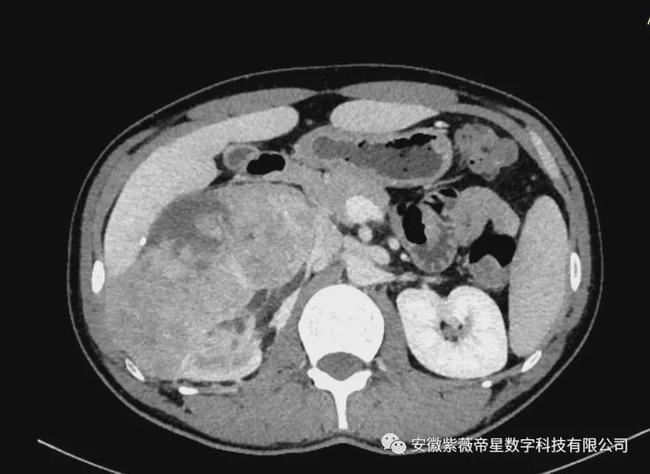

横断面

临床病史: 患者男,35岁,右肾区疼痛三月余,入院检查CT显示,右肾中下极见巨大软组织密度团块影,长度约14.8cm,其内密度不均匀,增强扫描明显强化,与右侧肾盂、肾盏及输尿管移行部分界不清,贴近临近肝脏、下腔静脉。右侧肾盂、肾盏扩张、积水。右肾未见明显异常强化。